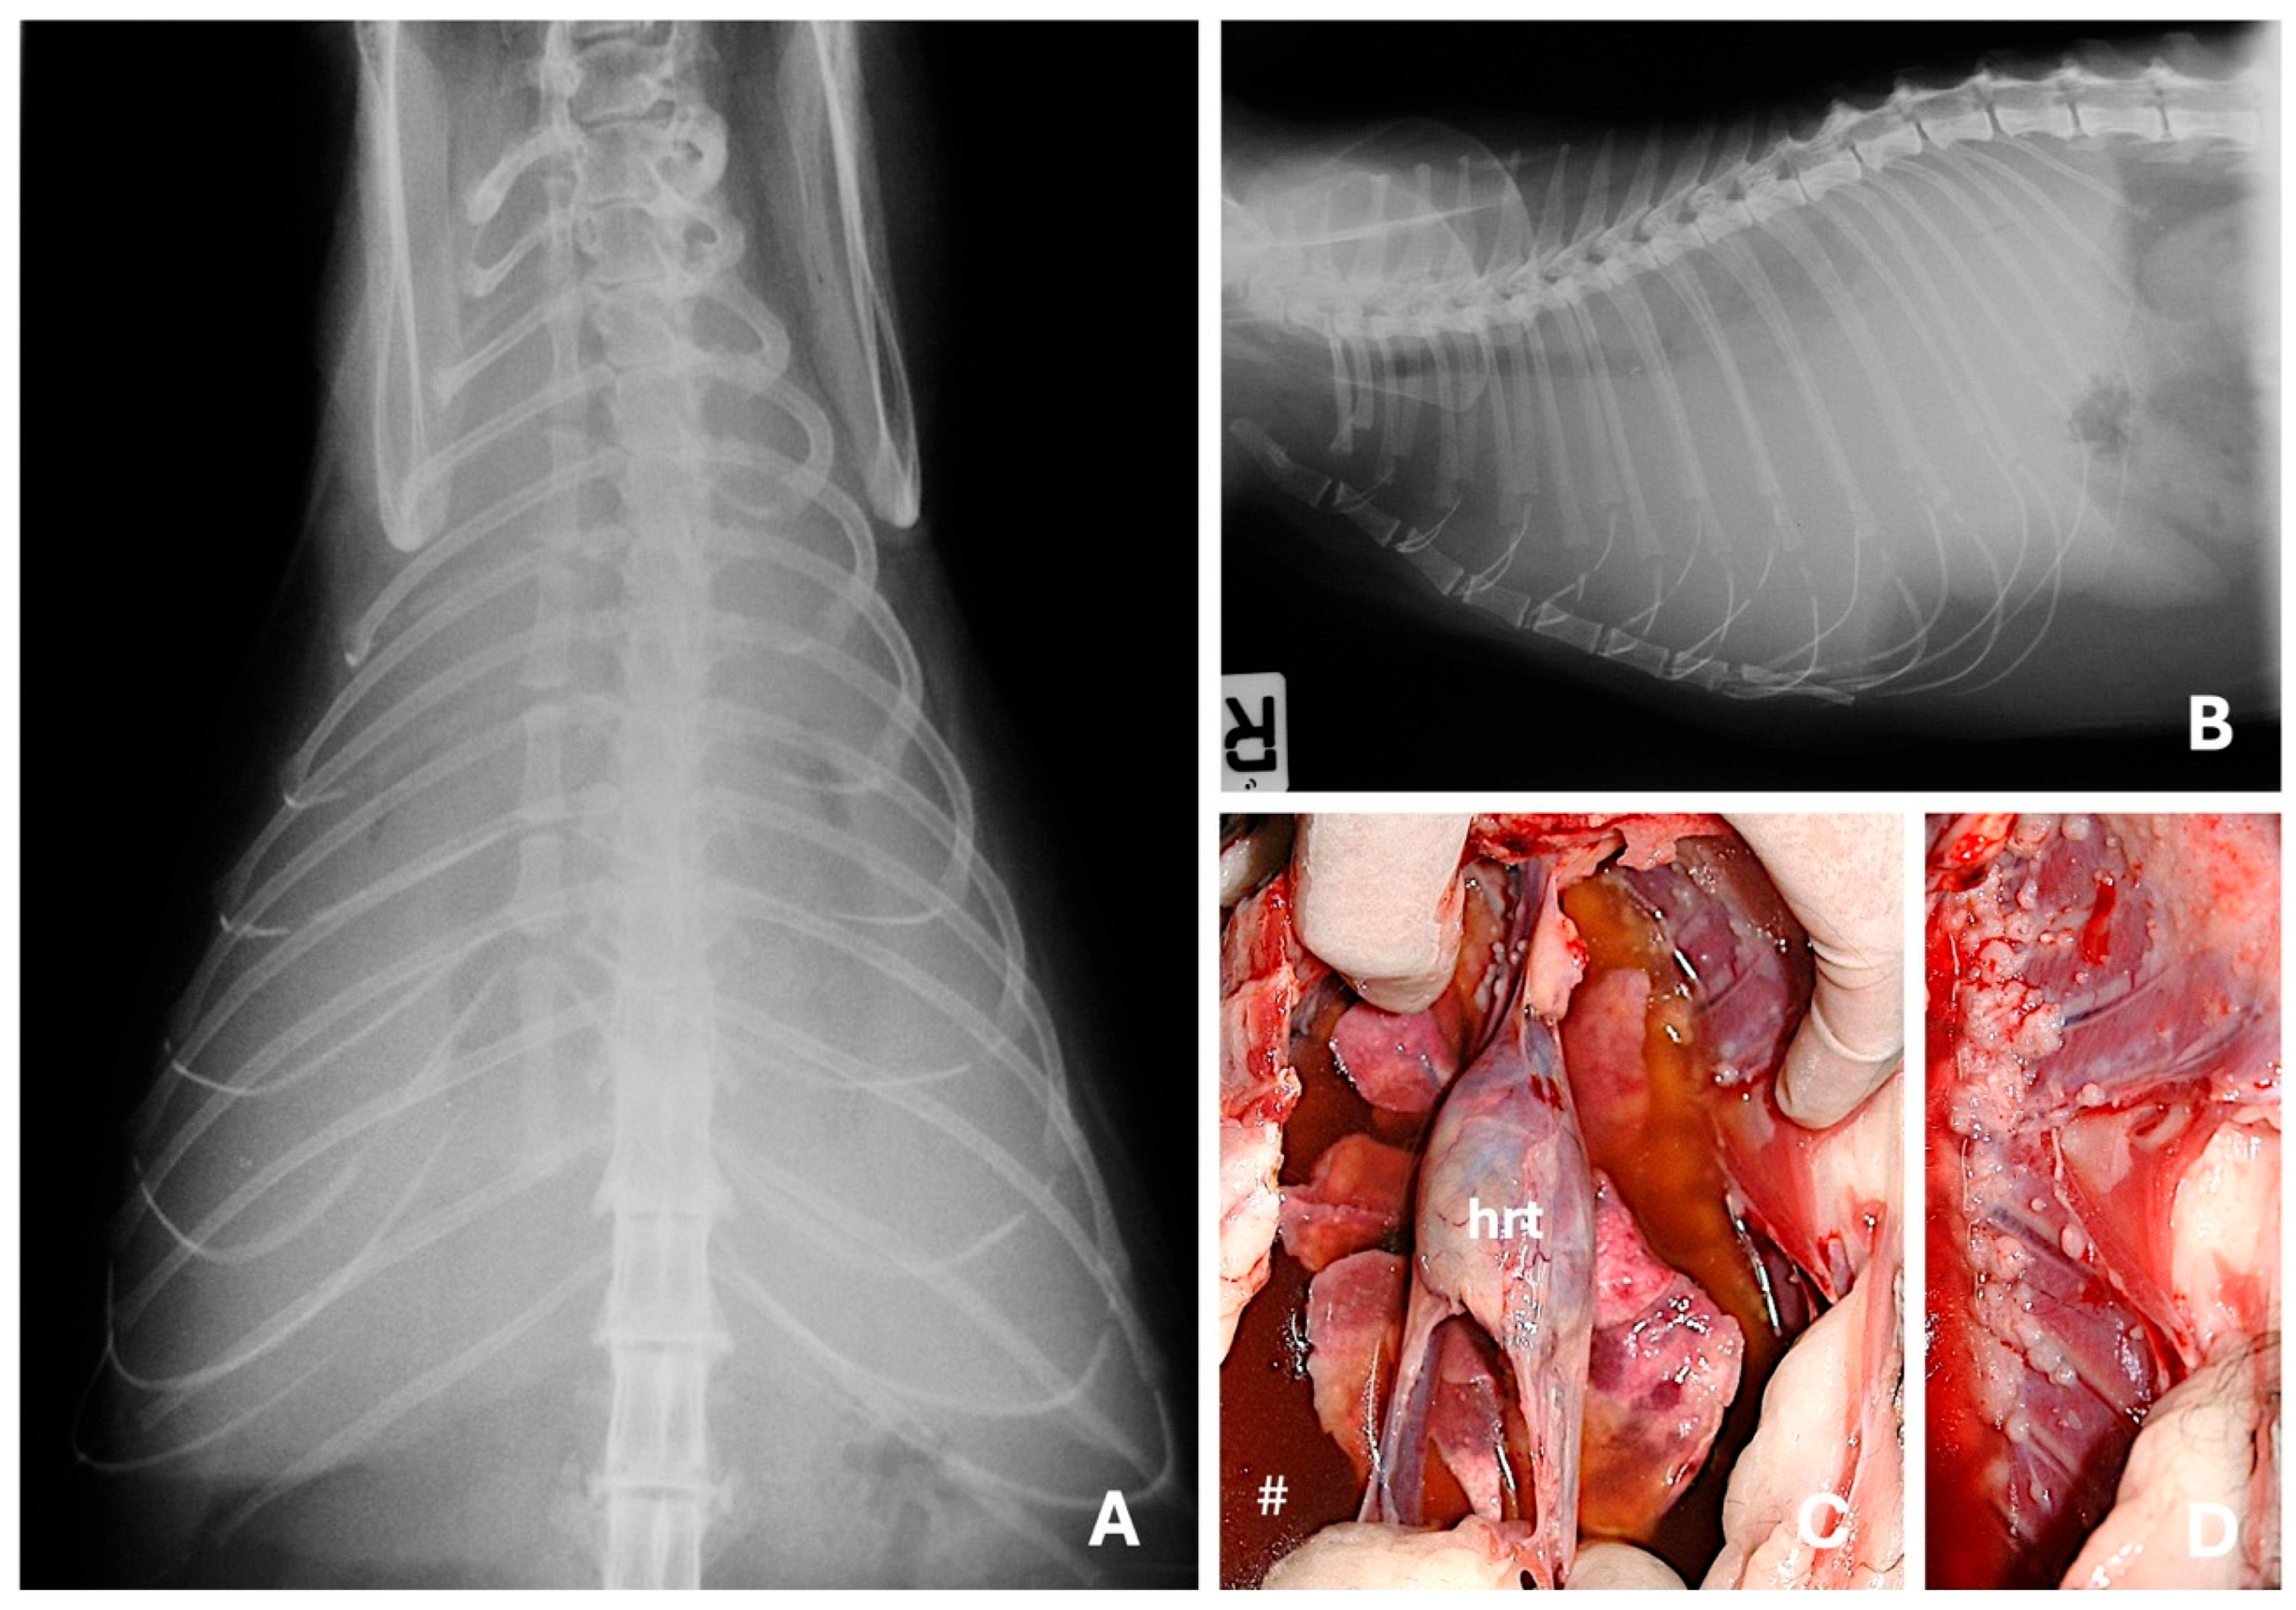

4.1. Radiography

- Aupperle, H.; März, I.; Ellenberger, C.; Buschatz, S.; Reischauer, A.; Schoon, H.-A. Primary and Secondary Heart Tumours in Dogs and Cats. J. Comp. Pathol. 2007, 136, 18–26. [Google Scholar] [CrossRef]